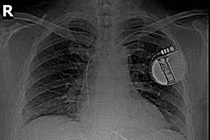

Cả hai tình trạng đều nguy hiểm, có nguy cơ gây biến chứng tụt huyết áp, rung nhĩ, suy tim, nhồi máu cơ tim, đột quỵ, tim ngừng đập. Giải pháp hiệu quả nhất trong trường hợp này là đặt máy tạo nhịp để đảm bảo nhịp tim bệnh nhân không quá chậm và dùng thuốc điều trị nhịp nhanh.

Trong vòng hơn hai giờ, ê-kíp tiến hành đặt máy tạo nhịp cho bà Quỳnh. Bác sĩ tạo một vết mổ nhỏ trên ngực của người bệnh, đưa các dây dẫn vào rồi gắn chúng vào thành ngoài tim. Tiếp đến, kết nối máy trợ tim với các dây dẫn này và đặt máy ở vị trí thích hợp trên vùng ngực bệnh nhân.

Sau khi đặt, máy có khả năng theo dõi, phát hiện hoạt động tạo nhịp của tim, tự động gửi xung điện qua dây dẫn đến tim mỗi khi nhận thấy tim đập quá chậm hoặc ngưng đập quá lâu. Các xung điện này kích thích làm tim đập đúng theo một tần số đã được cài đặt trước, đều đặn theo chu kỳ.

Bà Quỳnh tỉnh táo, hồi phục tốt sau can thiệp, nhịp tim duy trì ở mức 60-70 nhịp/phút. Bác sĩ kê toa thuốc hỗ trợ để khống chế cơn nhịp nhanh cho bà. Vết mổ khô, đường mổ nhỏ thẩm mỹ, không có nguy cơ nhiễm trùng. Bà xuất viện hai ngày sau đó.